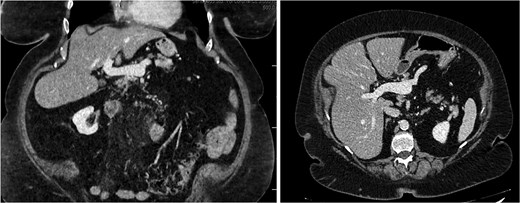

A 76-year-old female with a 3-day history of left upper abdominal pain, vomiting, and haematochezia. Her history included pulmonary embolism, multiple deep vein thromboses, with no ongoing anticoagulation, and an open partial colectomy for complicated diverticulitis a decade earlier. On admission, she was afebrile but tachycardic and showed localized tenderness in the left hypochondrium. Laboratory revealed leucocytosis with a white blood cell count (WBC) of 12 G/L, elevated C-reactive protein (CRP) of 46 mg/L, and hyperlactatemia of 2.6 mmol/l. Enhanced computed tomography (E-CT) revealed jejunal venous ischemia in the left upper quadrant, secondary to extensive porto-mesenteric thrombosis with reduced bowel wall enhancement, distention, and free intraperitoneal fluid (Fig. 1). She was managed conservatively with unfractionated heparin (UFH) with a bolus of 5000 U/l followed by 30 000 U/l/24 h (target INR 0.35–0.7), Piperacillin-Tazobactam, and bowel rest. After 48 h of monitoring in the intensive care unit (ICU), she exhibited marked biological and clinical improvement. E-CT on the third day showed restored bowel wall enhancement and stable porto-mesenteric thrombosis (Fig. 2). She was discharged on therapeutic low molecular weight heparin (LMWH) with enoxaparin sodium 120 mg every 12 h. At the 3-month follow-up, E-CT revealed near-complete thrombus resolution, without intestinal sequelae (Fig. 3).

Follow-up E-CT 72 h after conservative management in the first patient. Dashed arrows show improved viability of the small bowel with bowel wall enhancement. White arrows revealed the stability of the extended porto-mesenteric thrombosis.